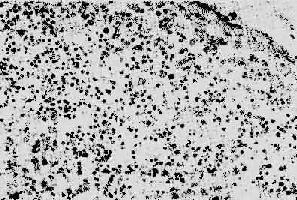

1.淋巴样组织的变化早期及中期,淋巴结肿大。镜下,最初有淋巴滤泡明显增生,生发中心活跃,髓质出现较多浆细胞。随后滤泡的外套层淋巴细胞减少或消失,小血管增生,并有纤维蛋白样物质或玻璃样物质沉积,生发中心被零落分割。副皮质区的淋巴细胞(CD4+细胞)进行性减少,代之以浆细胞浸润。晚期的淋巴结病变,往往尸检时才能看到,呈现一片荒芜,淋巴细胞,包括T、B细胞几乎均消失殆尽,无淋巴滤泡及副皮质区之分,仅有一些巨噬细胞和浆细胞残留(图4-15)。有时特殊染色可显现大量分枝杆菌、真菌等病原微生物,却很少见到肉芽肿形成等细胞免疫反应性病变。

AIDS淋巴结

图4-15 AIDS淋巴结

淋巴细胞明显减少,无淋巴滤泡及副皮质区之分